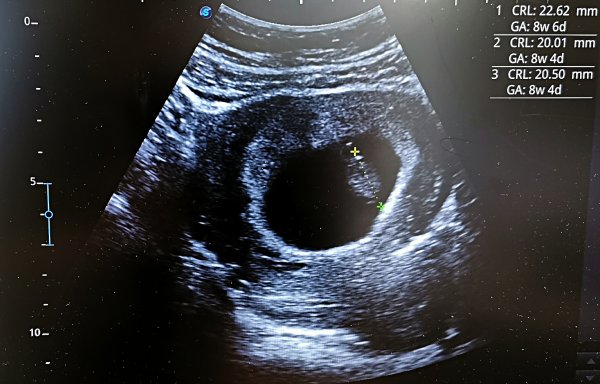

En bebis på rett plass, som vokser som den skal

Da trekker vi et lettelsens sukk, og gleder oss over denne nyheten.